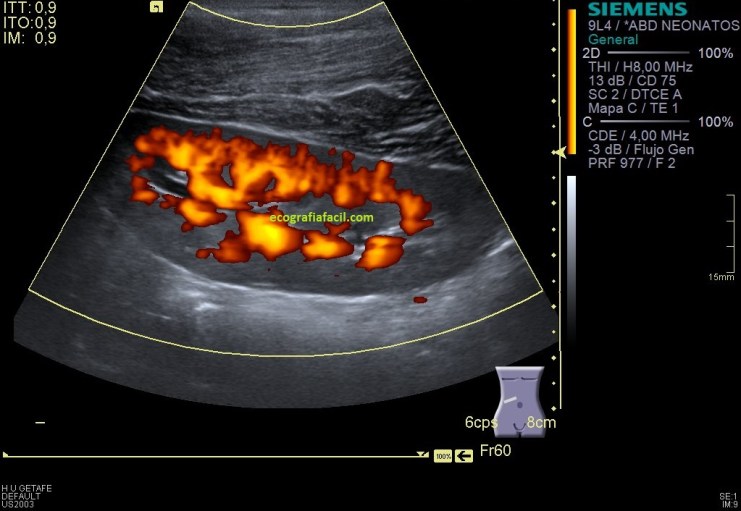

En la imagen 9 y la 10 del RD valoramos la vascularización cualitativa del órgano, vemos que su vascularización es rica, homogénea, de aspecto normal con las dos técnicas. Lógicamente en modo angio o doppler power vemos una vascularización más importante ya que a la vascularización de flujos rápidos (Doppler Color) le sumamos la vascularización de flujos más lentos (Doppler power).